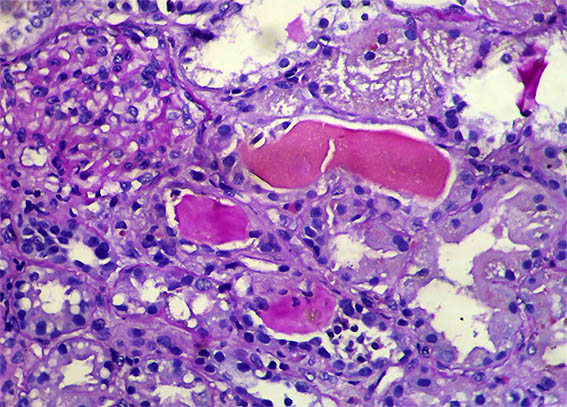

A 40-year-old man presented with severe acute liver failure secondary to hepatitis A virus infection, and acute kidney injury.

More relevant laboratory tests: thrombocytopenia (76,000), hyperbilirubinemia (7.1 mg/dL), transaminitis (1.830 U/L and 2.320 U/L), and elevated INR. Serum creatinine: 5.2 mg/dL, BUN: 78 mg/dL, proteinuria: 100 mg/dL, without microhematuria.

A kidney biopsy was performed. Look at the images.

Figure 6. H&E, X400.

Figure 7. H&E, X400.

Figure 8. H&E, X400.

Direct immunofluorescence for IgA, IgG, IgM, C3, C1q, kappa and lambda: Negative. Iron stain: negative.